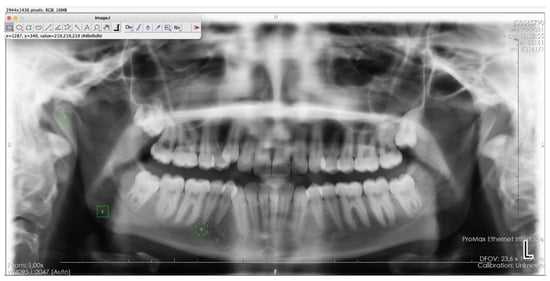

The chosen ROIs are in line with established anatomical landmarks used in prior fractal analysis studies. Ensuring consistency and comparability across research [9,10,12,13,14,15]. To ensure consistency and reliability in this study, a single researcher consistently cropped the defined ROI from the right side for each patient. The selected ROI was obtained by cropping a 64 × 64 pixel frame over the raw image using ImageJ software, with trabecular bone selected from the mandibular condyle’s geometric center (ROI1), the angulus region below the mandibular canal (ROI2), and the distal regions near the mental foramen (ROI3). To minimize variability introduced by different observers, each ROI was measured twice by the same researcher with a two-week interval. Intraobserver reliability was assessed using the Intraclass Correlation Coefficient (ICC), confirming the consistency of the measurements (Figure 2) [9,10]. (e.g., grammar, spelling, punctuation, and formatting) does not need to be declared.

Figure 2. ROI1, ROI2, and ROI3 areas selected on a panoramic radiograph using ImageJ software. 1: The mandibular condyle’s geometric center (ROI1), 2: The angulus region below the mandibular canal (ROI2), 3: The distal regions near the mental foramen (ROI3).